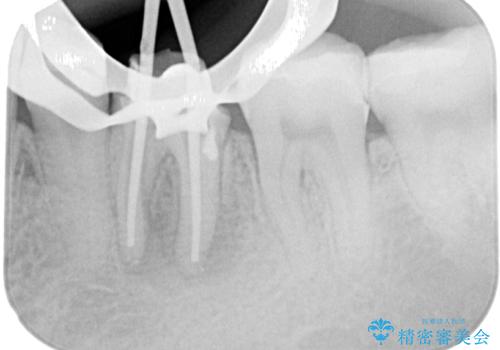

レントゲン写真などの診察を行った結果、根管治療が必要であったため、現在のクラウンを除去し、根管治療を行うこととしました。

根管治療後は症状を確認し、速やかにオールセラミッククラウンにて補綴治療を行うこととしました。